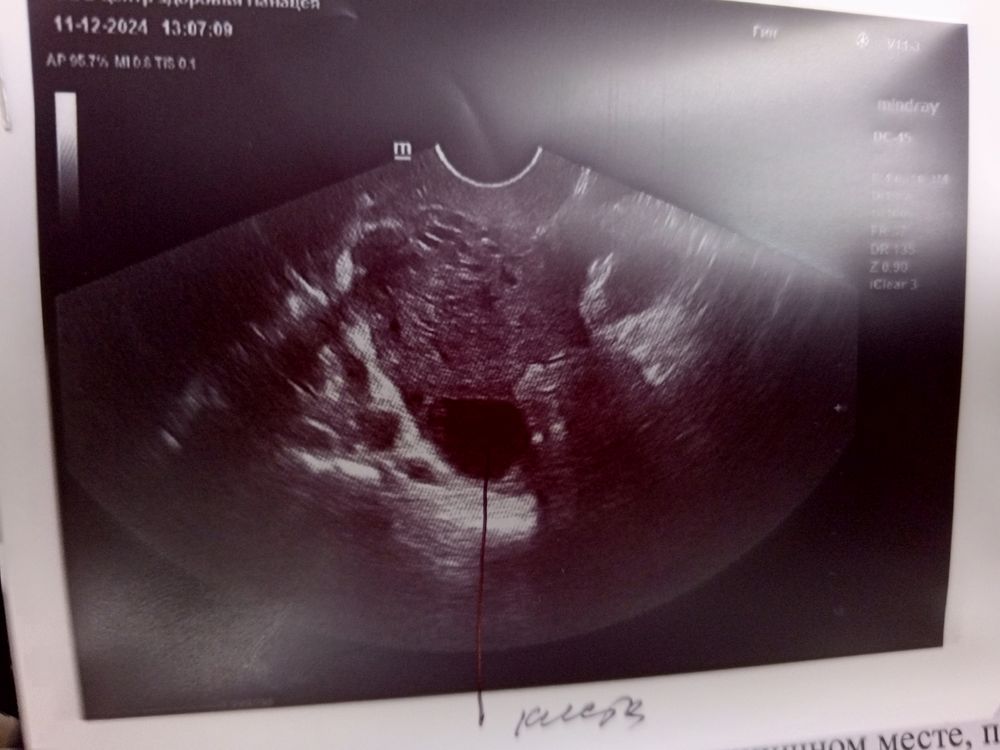

УЗИ на 27 дц

HelenA, киста

Мышонок, да, я вижу, на приеме узист сказала по поводу бтт, она сказала что есть киста но может это жёлтое тело но почему в правом когда доминант был в левом